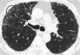

Usual interstitial pneumonia (UIP) is a form of lung disease characterized by progressive scarring of both lungs. The scarring (fibrosis) involves the supporting framework (interstitium) of the lung. [Source: Wikipedia ]